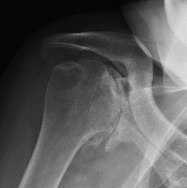

Medial migration with extremely deficient medial bone stock